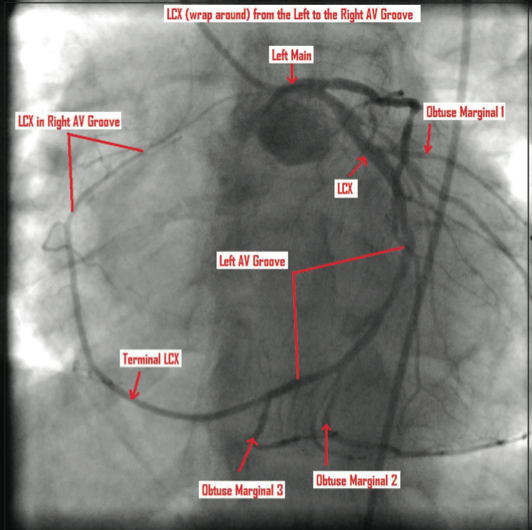

The catheterization and angiogram showed a patent left main coronary artery that bifurcated into the left anterior descending (LAD) and the left circumflex (LCX). The LAD had a mid 50% stenosis and the LCX was a large-sized vessel that gave off three obtuse marginal (OM) branches and continued distally into the right

side of the heart, filling the right coronary artery (RCA) from the distal end retrograde. The LCX had a mid 70-80% lesion that was confirmed by intravascular ultrasound (IVUS). The right coronary artery had no ostium and received retrograde filling via the LCX, continuing distally into the right myocardium. The LCX 80% mid stenosis was successfully revascularized with deployment of two drug-eluting stents. The patient was placed on post-procedure clopidogrel, simvastatin, beta blockers, and nitroglycerin.